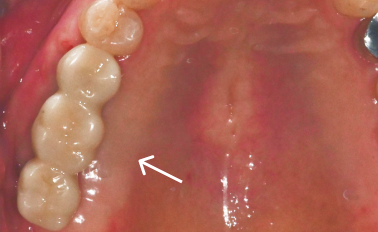

어금니임플란트 맞춤형으로 진행했을 때

골든타임을 놓치면 안되는 이유